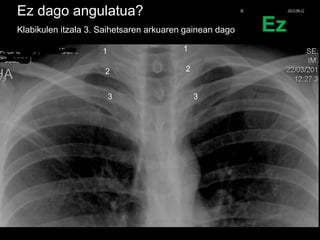

Ez dago angulatua?

Klabikulen itzala 3. Saihetsaren arkuaren gainean dago

1

2

3

Ez